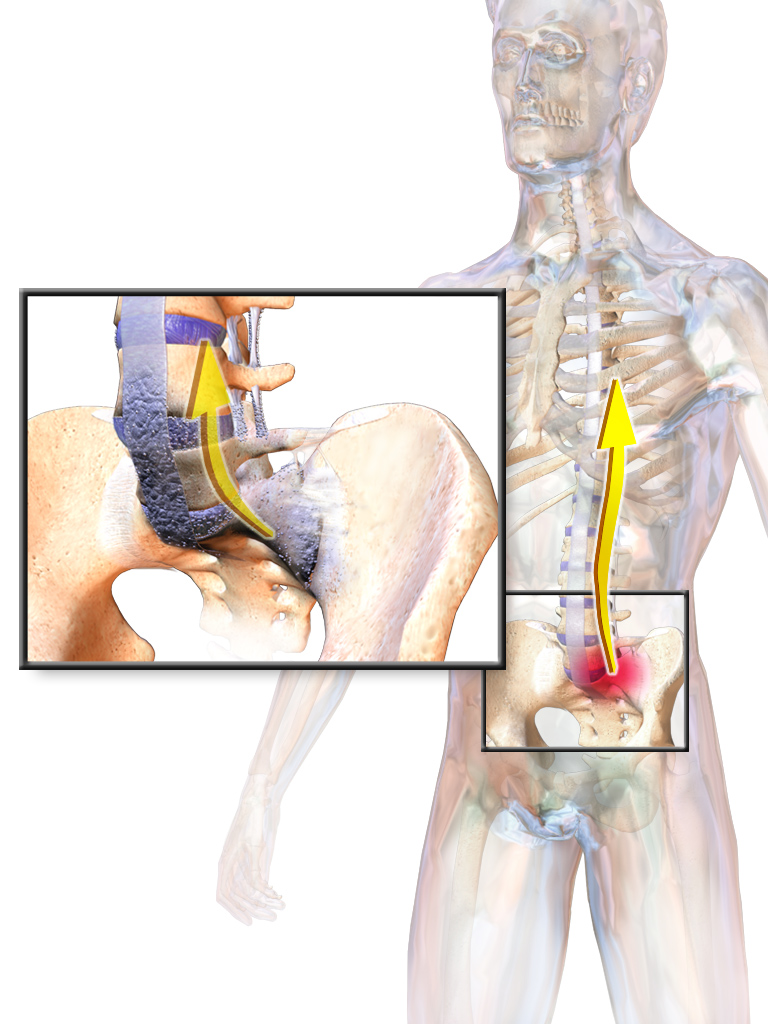

강직성 척추염은 척추의 어느 부분에서나 또는 척추 전체에서 발생할 수 있으며, 종종 천장관절에서 엉덩이 또는 허벅지 뒤쪽으로 통증이 국소적으로 나타난다. 엉덩이와 어깨의 관절염도 발생할 수 있다. 18세 이전에 이 질환이 나타나는 경우, 강직성 척추염은 무릎과 같은 큰 하지 관절의 통증과 부기를 유발할 가능성이 더 높다.[28] 사춘기 이전의 경우에는 발뒤꿈치 통증과 골 부착부위병증이 흔히 발생하는 발목과 발에서도 통증과 부기가 나타날 수 있다.[28] 덜 흔한 증상으로는 천골 신경근초의 확장증이 있다.[11]

단순 X-ray에서 가장 초기에 나타나는 변화는 천장관절의 침식과 경화이다.[23] 침식이 진행되면 관절 공간이 넓어지고 뼈가 경화된다. X-ray 척추 사진은 신데스모파이트라고 하는 뼈 가시 형성으로 척추가 사각형이 되는 것을 보여줄 수 있으며, 이는 대나무 척추 모양을 유발한다. X-ray 진단의 단점은 강직성 척추염의 징후와 증상이 일반적으로 단순 X-ray에서 확인 가능한 변화가 나타나기 7~10년 전에 이미 나타난다는 것이다. 이는 적절한 치료법을 도입하기 전에 최대 10년의 지연이 발생할 수 있음을 의미한다.[23]